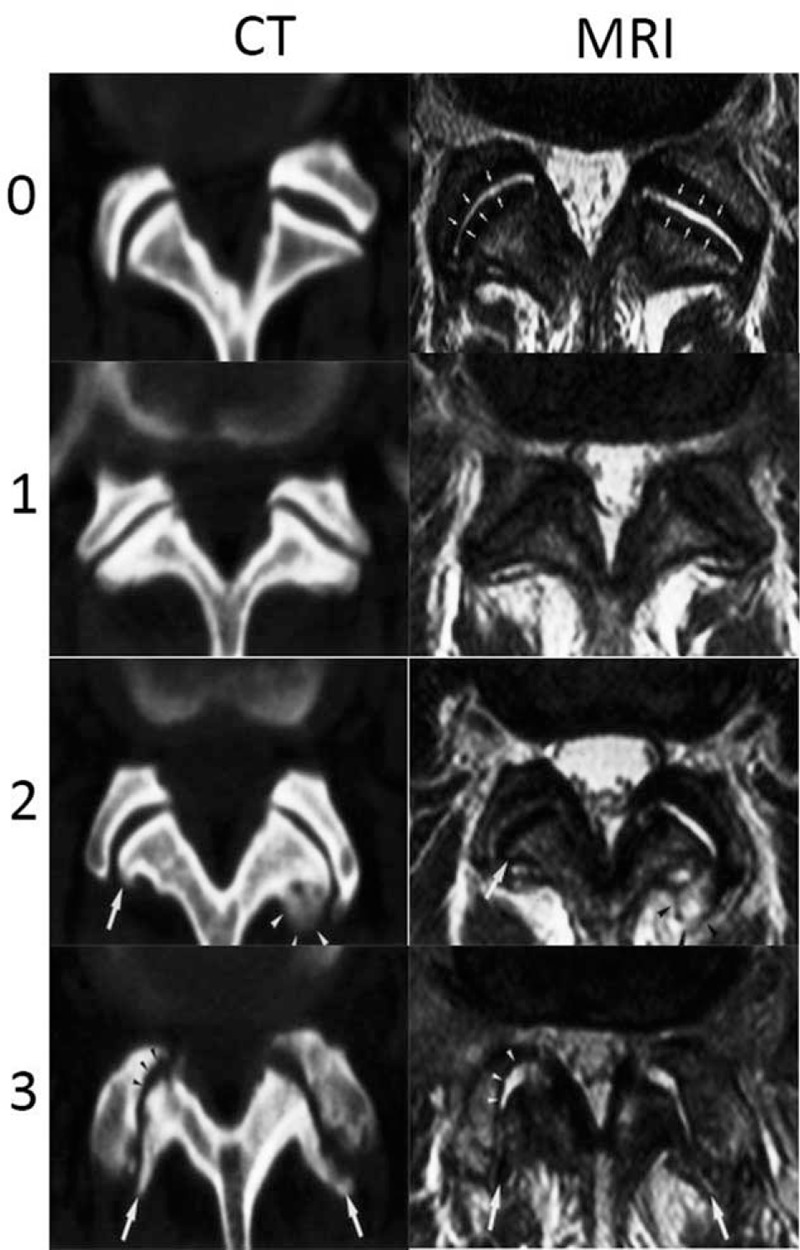

2.5. Lumbar facet joint degenerative grading in MRI

We used the criteria proposed by Weishaupt, which defined the degree of facet degeneration using CT combined with MRI (Fig. 4).[15,16] Grade 1, normal facet joint space (2–4 mm width); Grade 2, narrowing of the facet joint space (<2 mm), small osteophytes, and/or mild hypertrophy of the articular process; Grade 3, narrowing of the facet joint space, moderate osteophytes, moderate hypertrophy of the articular process, and/or mild subarticular bone erosions; and Grade 4, narrowing of the facet joint space, large osteophytes, severe hypertrophy of the articular process, severe subarticular bone erosions, and/or subchondral cysts. All grading data were independently evaluated by an experienced radiologist (15 years of experience with MRI) and an experienced orthopedic spine surgeon (10 years of specialization in spine surgery), and grading was performed using the double-blind method.

Figure 4.

The Weishaupt grading of facet joint degeneration: Grade 0, normal facet joint space (2–4 mm width); Grade 1, narrowing of the facet joint space (<2 mm), mild osteophytes, and/or mild hypertrophy of the articular process; Grade 2, narrowing of the facet joint space, moderate osteophytes, moderate hypertrophy of the articular process, and/or mild subarticular bone erosions; and Grade 3, narrowing of the facet joint space, large osteophytes, severe hypertrophy of the articular process, severe subarticular bone erosions, and/or subchondral cysts.